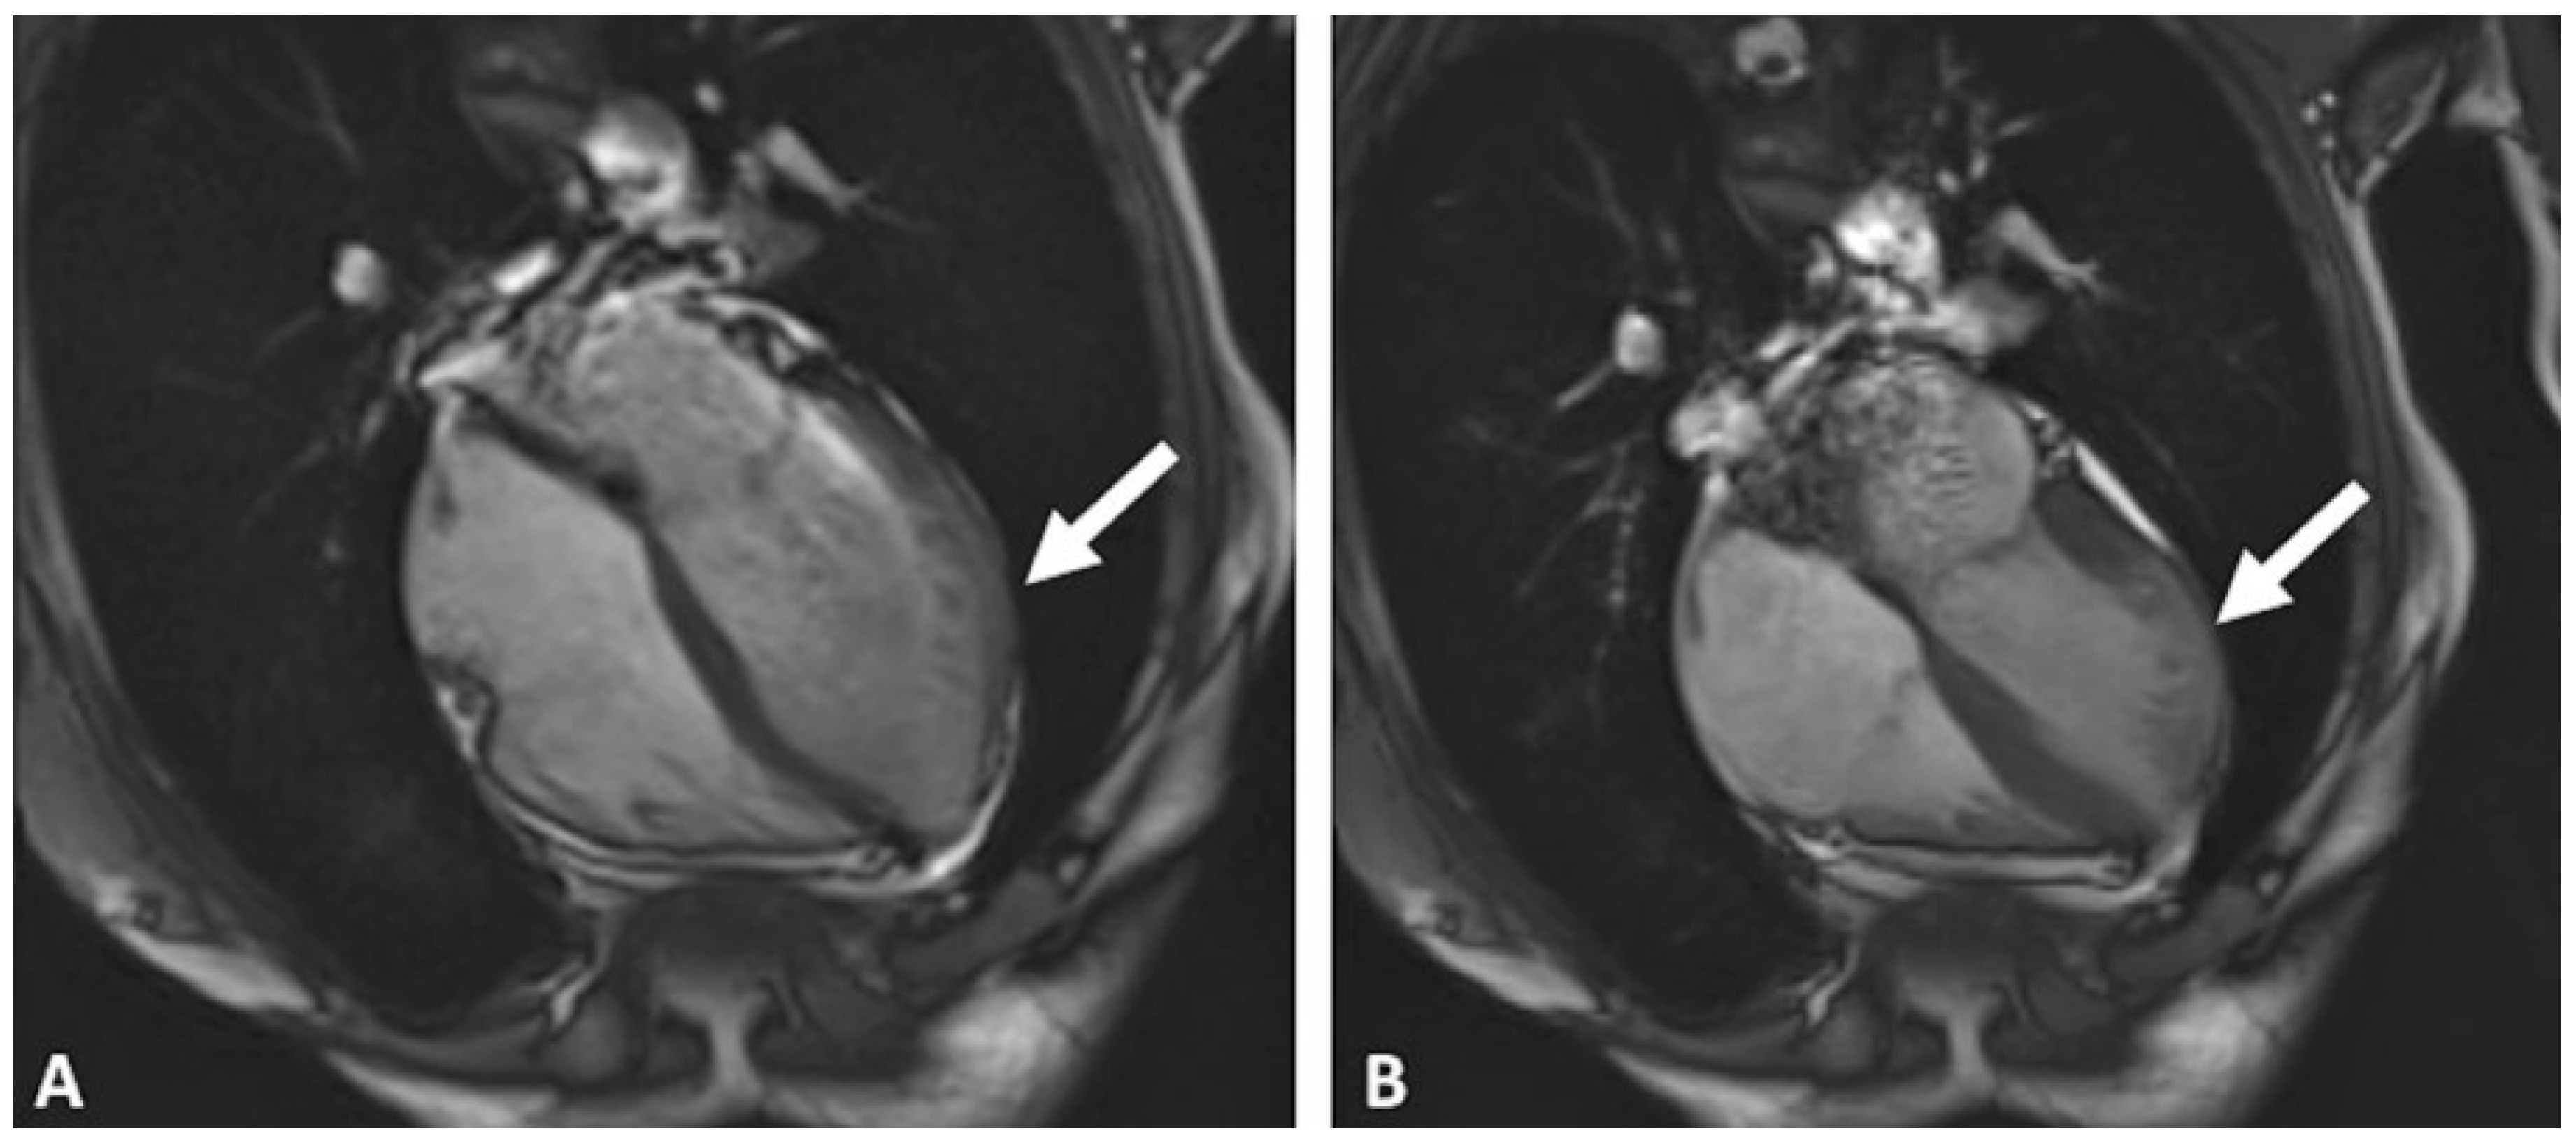

Case report